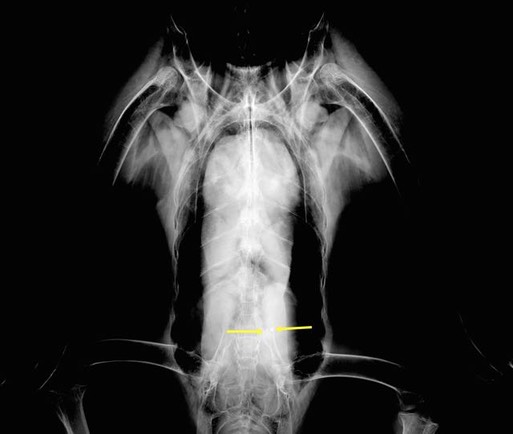

A radiograph shows what appear to be two pieces of lead in the eagle’s ventriculus (gizzard). We are attempting to rehydrate her in hopes that she will cast a pellet and expel the lead. One of the side-effects of lead toxicity is to cause the gut to shut down. We are definitely fighting an up-hill battle.

Below is a radiograph enhanced by Dr. Jeff Cooney to better show the lead fragments.